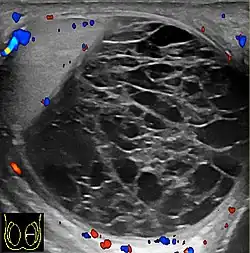

Hemoscrotum can follow trauma (such as a straddle injury) or can be a complication of surgery. It is often accompanied by testicular pain. It has been reported in patients with hemophilia and following catheterization of the femoral artery. If the diagnosis is not clinically evident, transillumination (with a penlight against the scrotum) will show a non-translucent fluid inside the scrotum. Ultrasound imaging may also be useful in confirming the diagnosis. In severe or non-resolving cases, surgical incision and drainage may be required. To prevent recurrence following surgical drainage, a drain may be left at the surgical site.

Current research is ongoing for proper diagnosis and helping to differentiate among other conditions. Doppler ultrasound in a retrospective study was shown to be helpful for differential diagnosis of patients with acute scrotum.[12] Accuracy of imaging studies is higher for the differential diagnosis of testicular torsion and epididmo-orchitis, which there can still be the possibility of misdiagnosis for hematoceles due to testicular torsion.[12] Further research in this area shows importance for surgical decision making in hematoceles.[12]